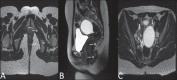

Magnetic resonance imaging is a method with high contrast resolution widely used in the assessment of pelvic gynecological diseases. However, the potential of such method to diagnose vaginal lesions is still underestimated, probably due to the scarce literature approaching the theme, the poor familiarity of radiologists with vaginal diseases, some of them relatively rare, and to the many peculiarities involved in the assessment of the vagina. Thus, the authors illustrate the role of magnetic resonance imaging in the evaluation of vaginal diseases and the main relevant findings to be considered in the clinical decision making process.